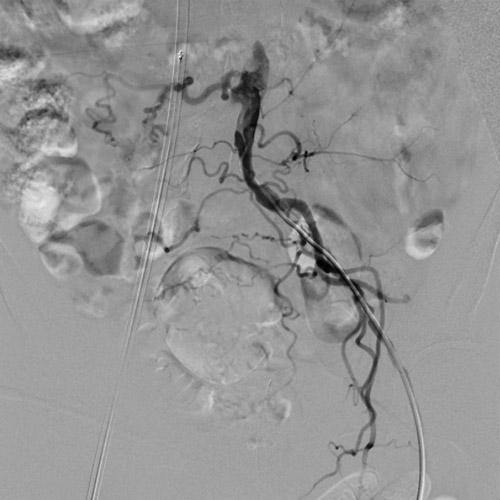

主訴は右足跛行(Ratherford3)、既往歴は高血圧、糖尿病、脂質異常症、心房細動であり、右CIA閉塞病変の治療を行うこととしたがEIAに動脈瘤があった(瘤部の血管径は約10mm)(図1、図2)。

左dRAからエコーガイド穿刺を行いGlidesheateh Slender7FrとR2P SlenGuideの組み合わせでアプローチを開始した。その際、カバードステント(シャフト長135cm)の留置を予定していたため、よりガイディングカテのシステム全長を短くするためにR2P SlenGuideに止血弁を組み合わせた。R2P SlenGuideが病変部に対してコアキシャルになり難く、バックアップは十分に取れなかったが、6gワイヤー(0,014“)で病変を通過後、Navifocus WRでintra-plaque内であることを確認し、Senri 3-40mm でプレ拡張を行った(図3)(図4)。